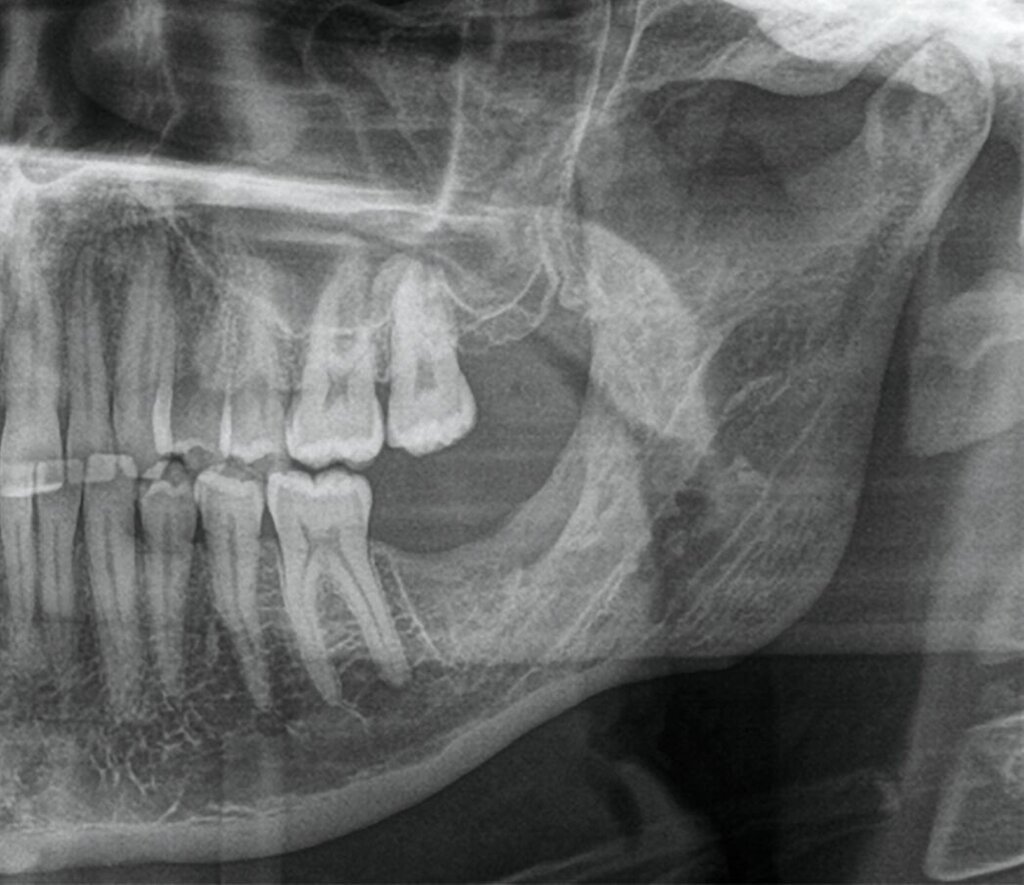

Die seitdem halbjährlich durchgeführten Nachkontrollen zeigen klinisch reizlose Verhältnisse und einen beschwerdefreien Patienten. Radiologisch fand sich eine fortschreitende knöcherne Ausheilung ohne Rezidivhinweise, wie in den Verlaufskontrollen unmittelbar postoperativ, nach einem Jahr und nach zwei Jahren dargestellt (Abbildung 5). Angesichts möglicher Spätrezidive wird die langfristige Nachsorge fortgeführt.